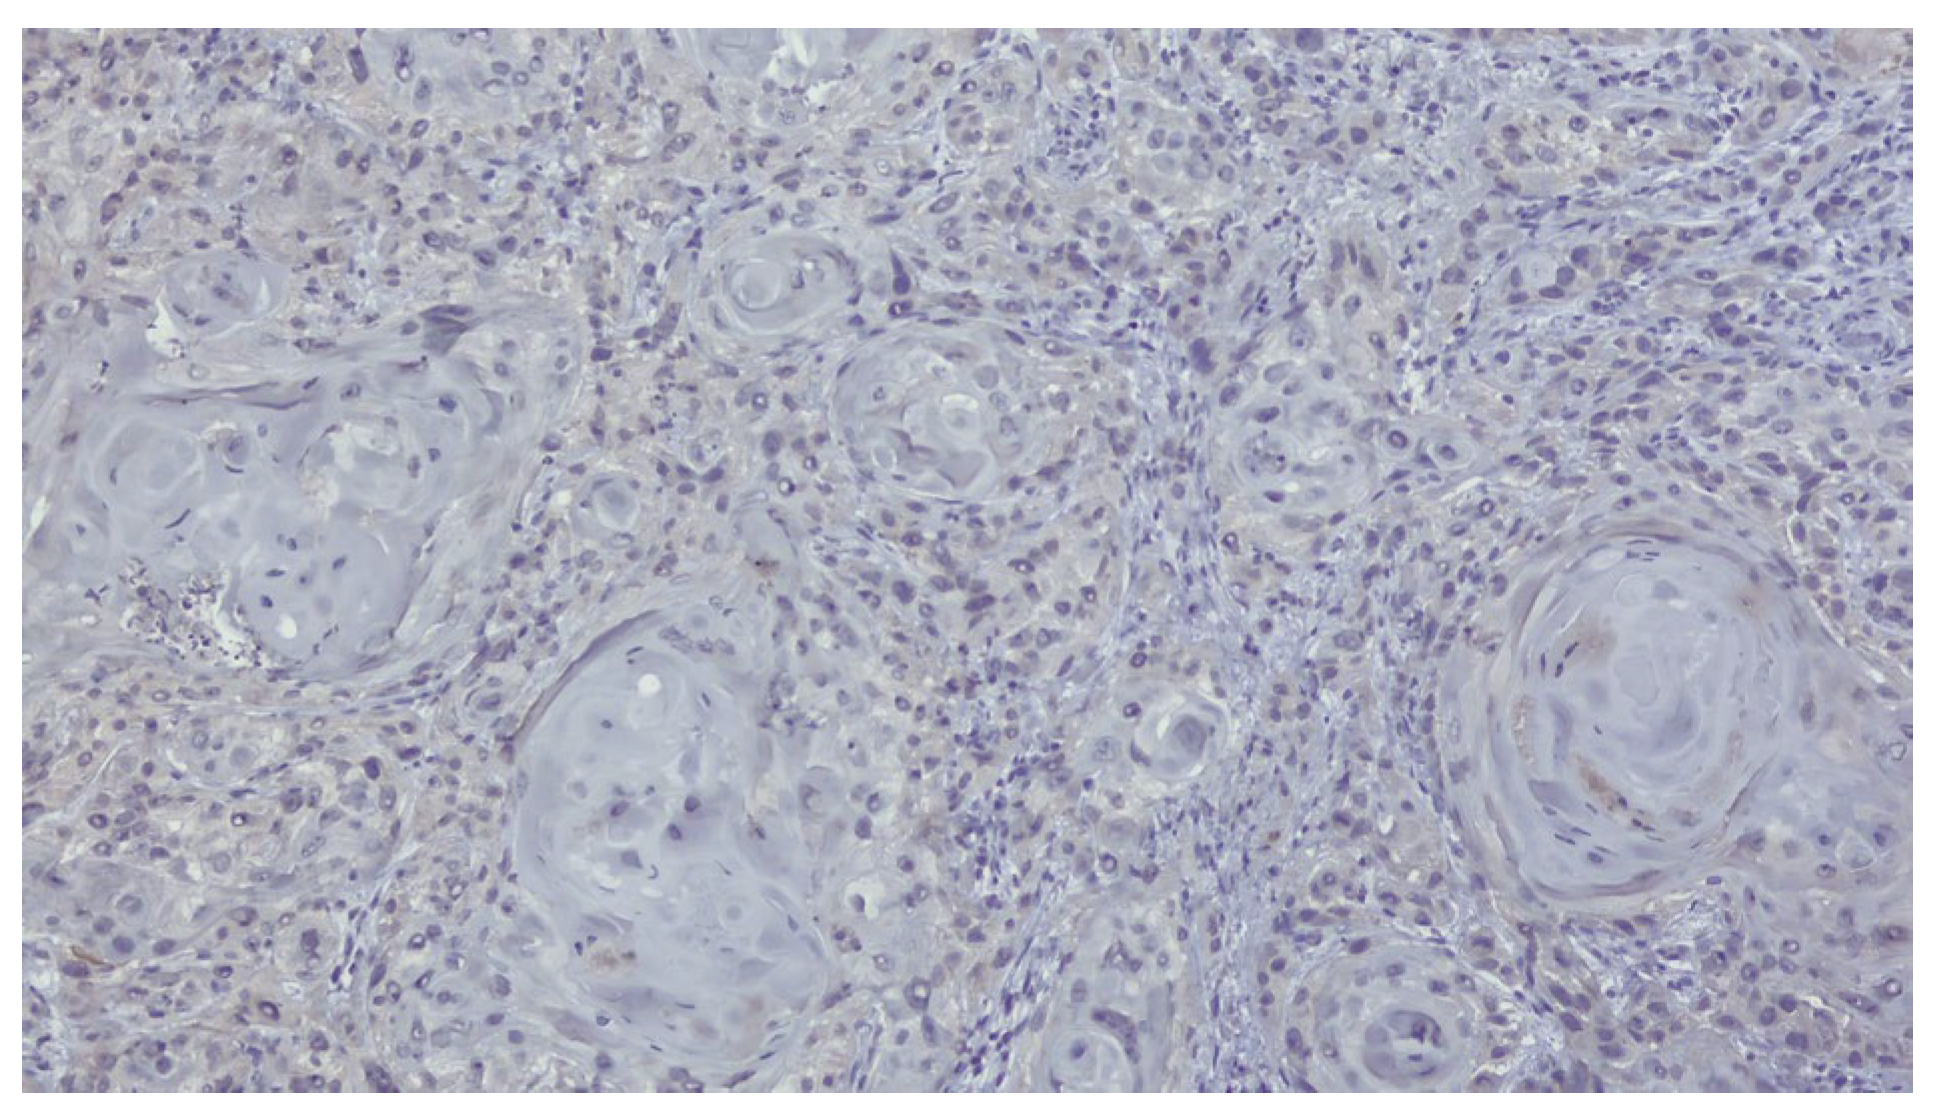

The patient was referred to the Department of Oral and Maxillofacial Surgery for further evaluation and management. Following an outpatient consultation and comprehensive clinical examination, no palpable cervical lymphadenopathy was identified on physical assessment. Incisional biopsy of the oral lesion was performed under local anesthesia and the histopathological analysis of the biopsy specimen subsequently confirmed the diagnosis of moderately differentiated keratinizing squamous cell carcinoma grade II Immunohistochemical staining for p16 was also performed and showed a negative result, indicating that the lesion was not HPV-related but more consistent with a conventional, tobacco-associated carcinogenesis pathway (Figure 2).

Figure 2.

Biopsy-immunohistochemical reaction-p16 marker-negative.

Definitive histopathological analysis of the surgical specimen confirmed a moderately differentiated keratinizing squamous cell carcinoma with evidence of perineural invasion (Figure 7). All surgical margins were free of tumor infiltration (R0 resection). Examination of the lymph nodes removed during selective neck dissection revealed no metastatic involvement (0 nodes). No evidence of distant metastasis was identified on preoperative imaging or postoperative staging, confirming a final pathological stage of pT3N0M0 (Stage III) according to the AJCC 8th edition.